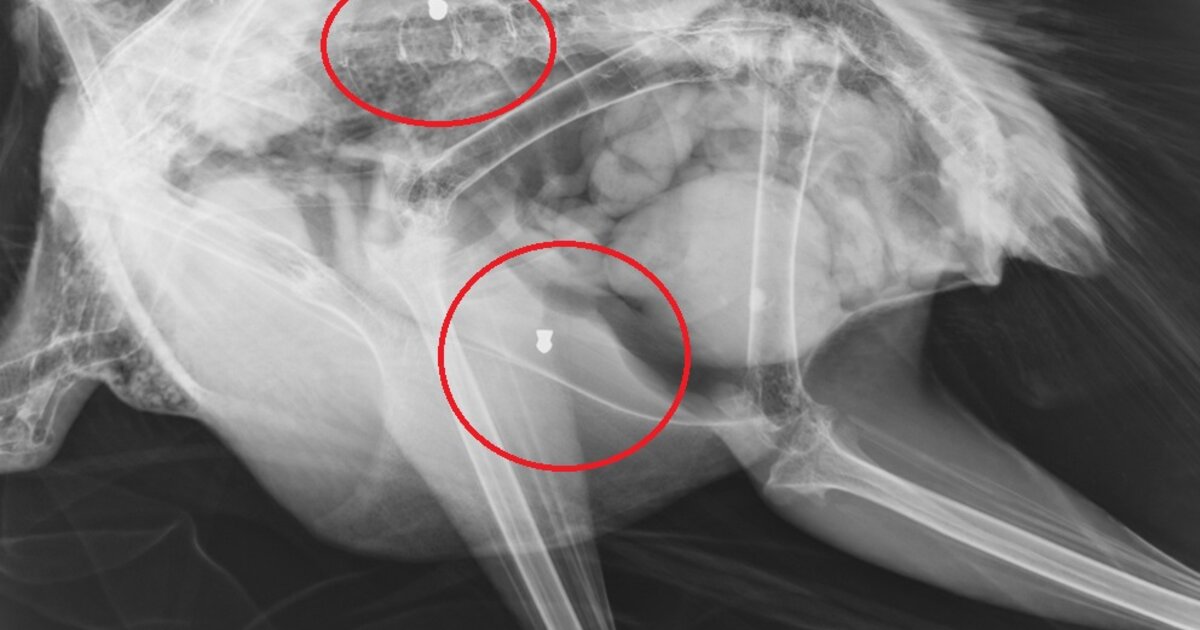

Το εντυπωσιακό πτηνό φέρεται να δέχθηκε πυροβολισμούς, γεγονός που επιβεβαίωσαν και σχετικές ακτινογραφίες που "έδειξαν" μάλιστα δυο βολίδες αεροβόλου κι ένα σκάγι.

Το παγώνι φέρεται να δέχθηκε πυροβολισμούς, γεγονός που επιβεβαίωσαν και σχετικές ακτινογραφίες που "έδειξαν" μάλιστα δυο βολίδες αεροβόλου κι ένα σκάγι.

"Το ζώο αυτό έχει πυροβοληθεί τρείς φορές, την ίδια ώρα ή διαφορετικές δεν μπορούμε να ξέρουμε, ούτε αν ο δράστης είναι ένας ή δύο ή τρεις, μέσα ή δίπλα σ έναν από τους πιο πολυσύχναστους αρχαιολογικούς χώρους της Κρήτης και της Ελλάδας γενικότερα" αναφέρει χαρακτηριστικά σε ανάρτηση του ο Σύλλογος ΑΝΙΜΑ.